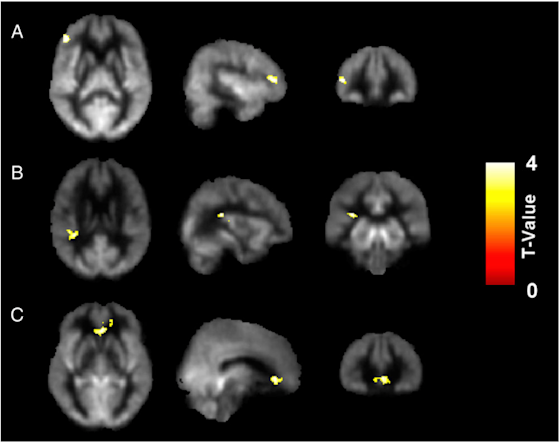

Figure 3 shows increases in brain blood flow in the (A) Frontal Gyrus, (B) Insula, and (C) Anterior Cingulate Cortex as a result of completing the gist reasoning training SMART.